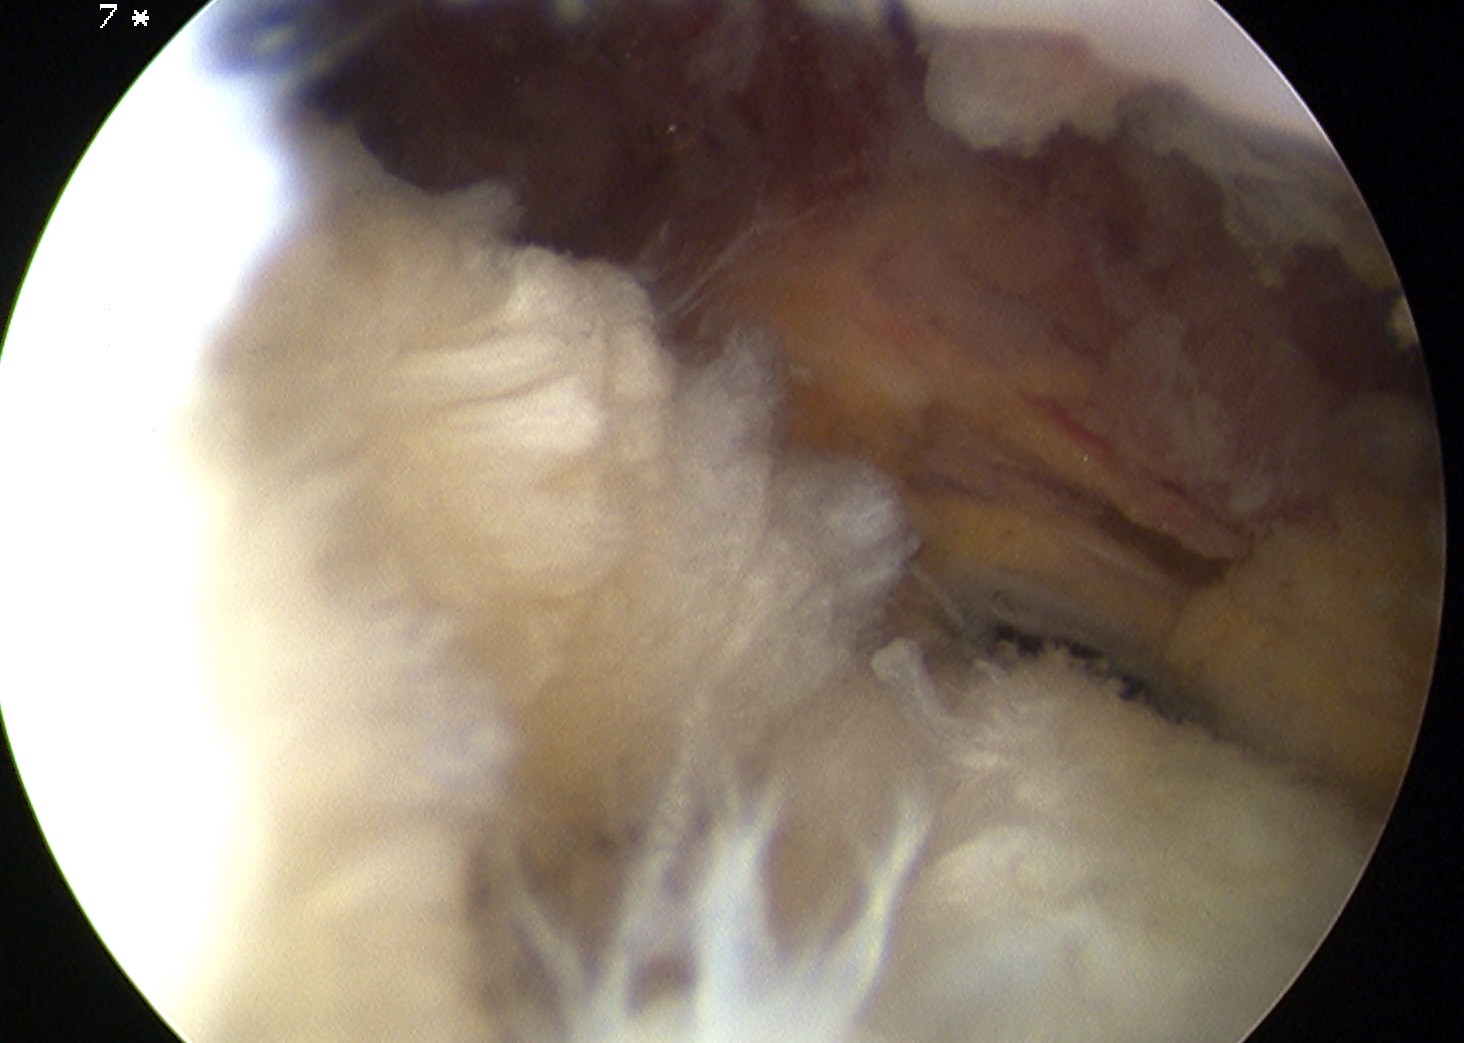

Bursal Sided

> 50% bursal sided tears with camer in subacromial space